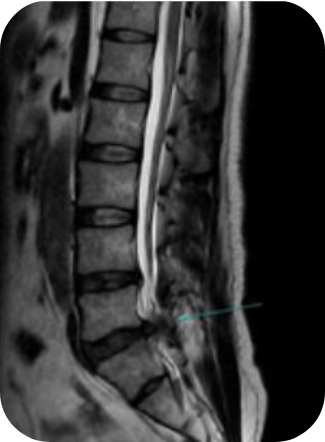

PELD

척추내시경

이 수술법이 처음 나온 지는 20년이 넘었습니다만 최근 들어 기기와 기술의 발전으로 각광을 받게 되었습니다. 피부에 약 7 mm 크기의 내시경을 넣어 수술을 하는 것으로 수술 후 회복이 매우 빠르다는 장점이 있습니다. 과거에는 터져 나온 디스크를 처리하지 못하는 한계를 보였으나 이제는 많이 발전하여 디스크의 여러 유형을 처리할 수 있어 수술의 성공률이나 환자의 만족도도 많이 높아졌습니다.

- 추간판탈출증